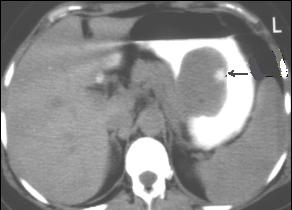

Lymphome gastrique :

Une epaississement diffuse a hypodense mais sans

stenose de l' estoma ( image TDM en coupe axiale ) .N'a

pas de rigidite a la region lesionaire |